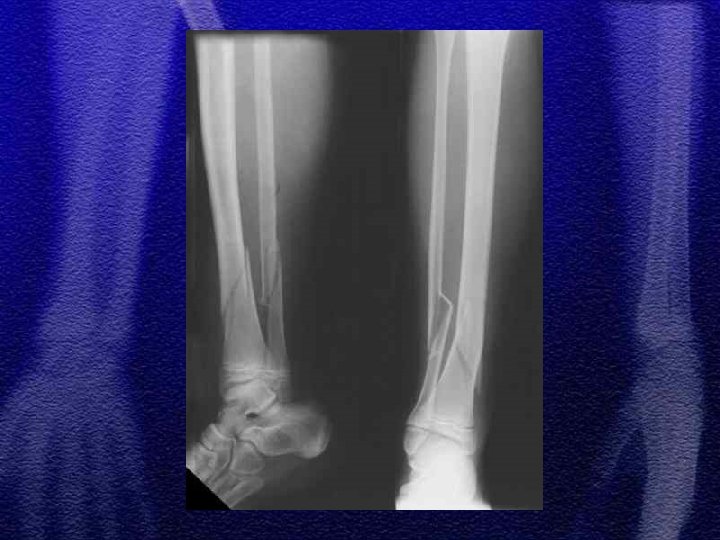

§ W zależności od mechanizmu urazu spotykamy różne typy złuszczeń od I do IV wg Saltera-Harrisa § Złuszczenia typu I i II leczenie zachowawcze gips - 4 tyg. § Złuszczenie typu III i IV leczenie operacyjne - śruby, druty Kirschnera § Złuszczenia wielopłaszczyznowe typ II i III występujące jednocześnie w nasadzie dalszej kości piszczelowej